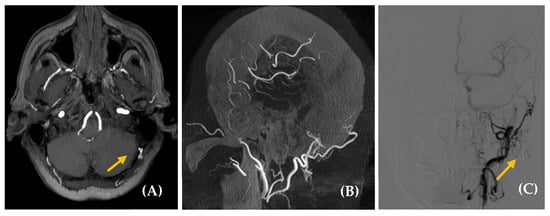

Figure 4. Dural arteriovenous fistula (dAVF) in a 65-year-old woman with a somatosound in the left ear, present for five years. The PT neither disappeared nor changed upon compression of the cervical vascular axis. MR angiography axial plane (image (A)) revealed findings suggestive of a dAVF (yellow arrow). Diagnostic–therapeutic arteriography (images (B), cone bean angio CT MPR in sagittal plane and (C), posteroanterior DSA view with injection of extracellular contrast agents) confirmed the presence of an AVF with arterial supply from the left occipital branch and superficial venous drainage to the left suboccipital region. Based on this finding, the fistula was embolized (yellow arrow, image (C)).